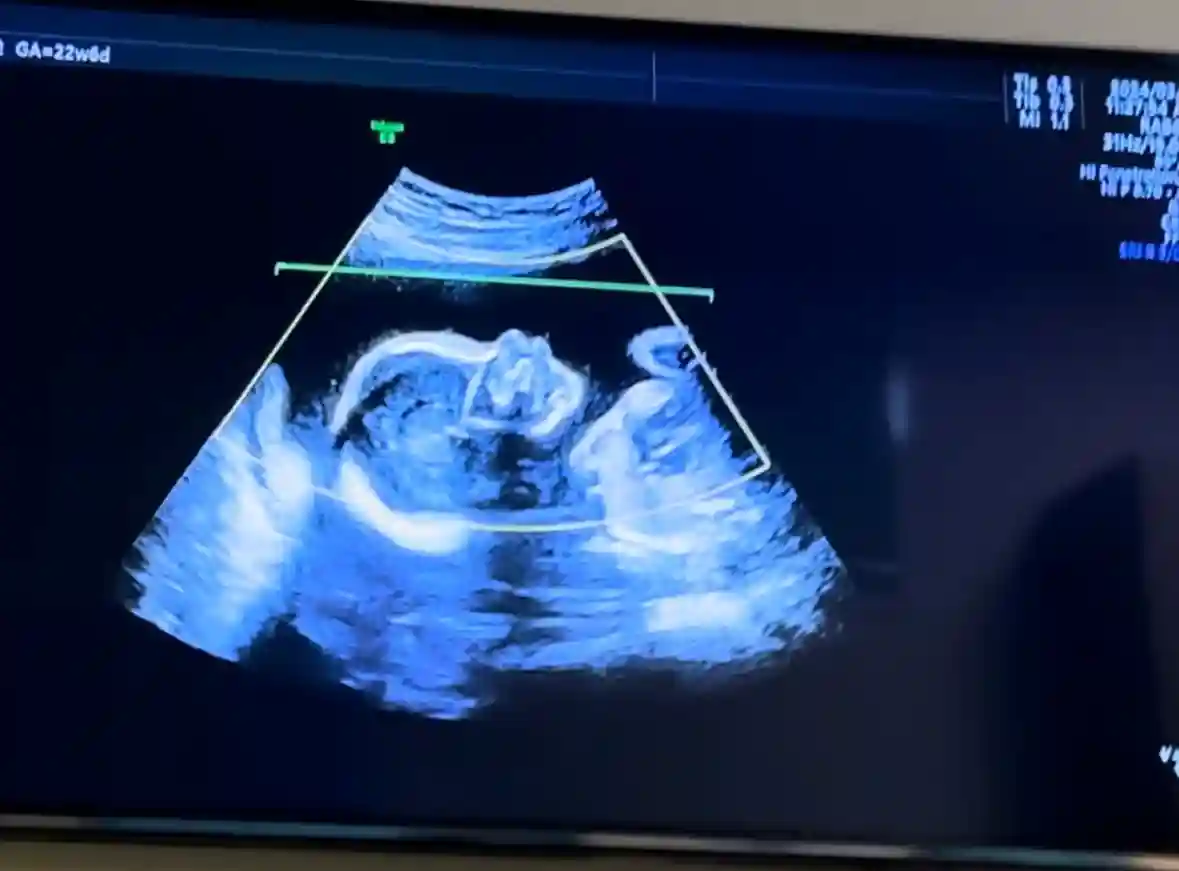

3.怀孕后肾炎各项指标会上涨吗这个得看自己情况 但是一定要在发现怀孕后立刻去医院看看 后续一个月复查一次 医生告诉我四 五个月最容易高血压引起尿蛋白增多 让我一天测一次血压